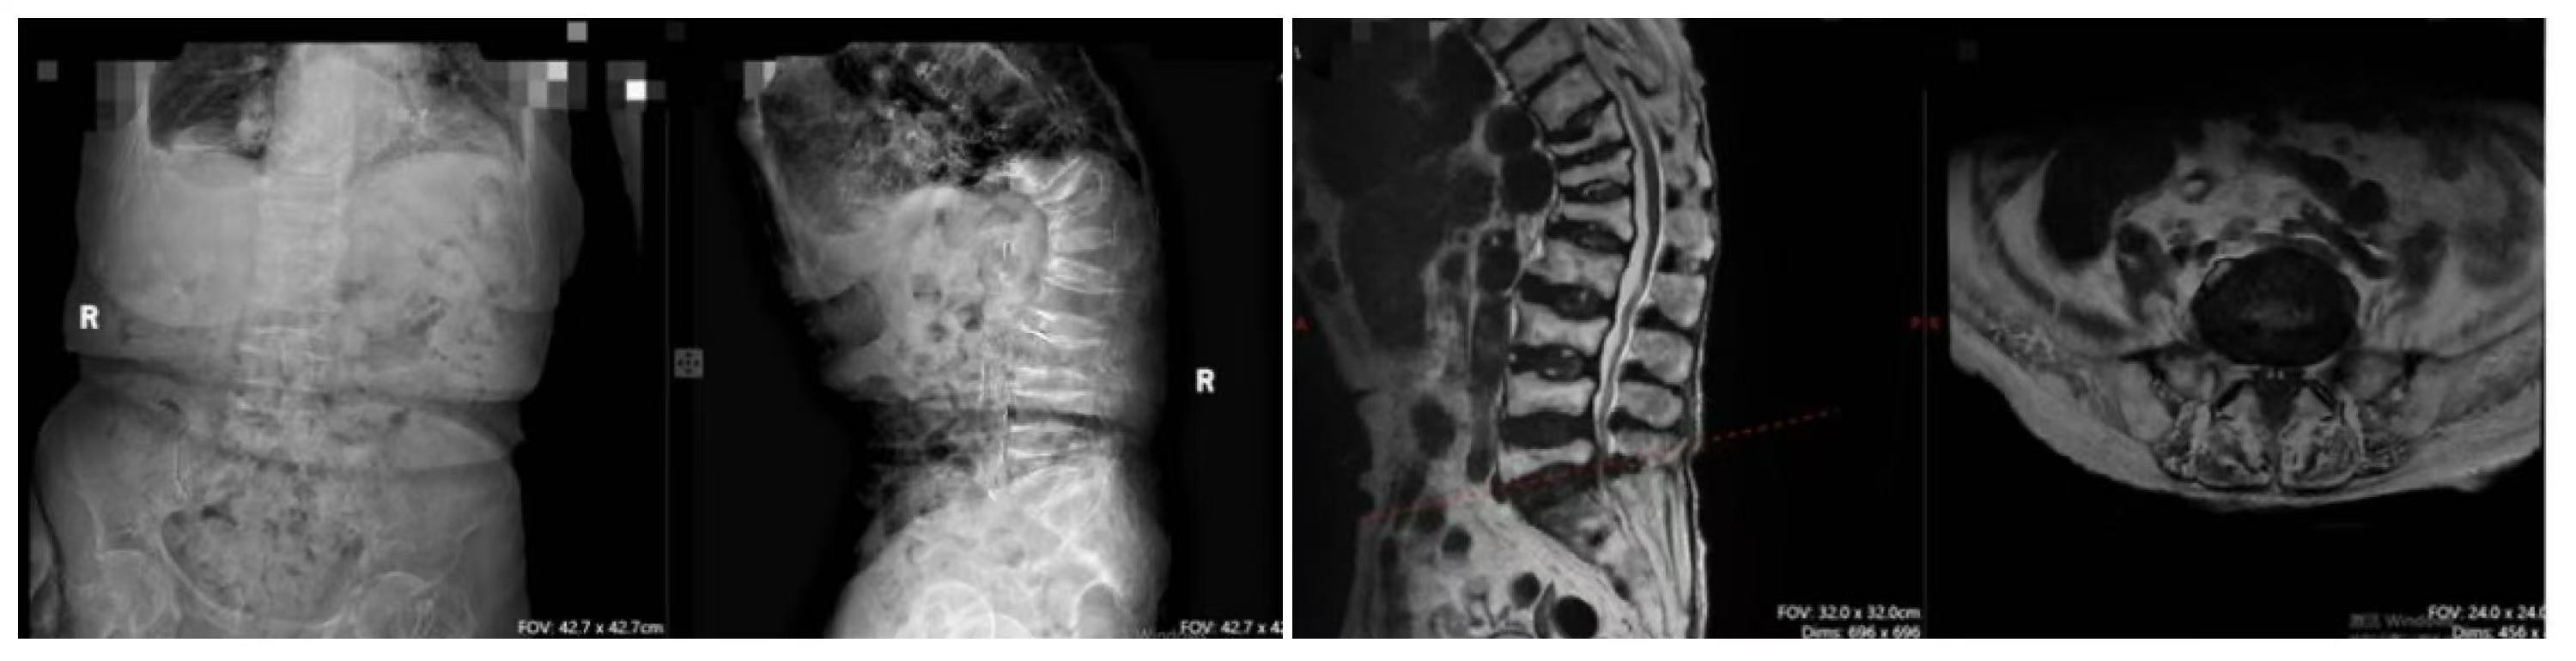

术前影像显示老人存在重度腰椎管狭窄合并脊柱畸形

术后CT可见手术节段椎管扩大减压充分